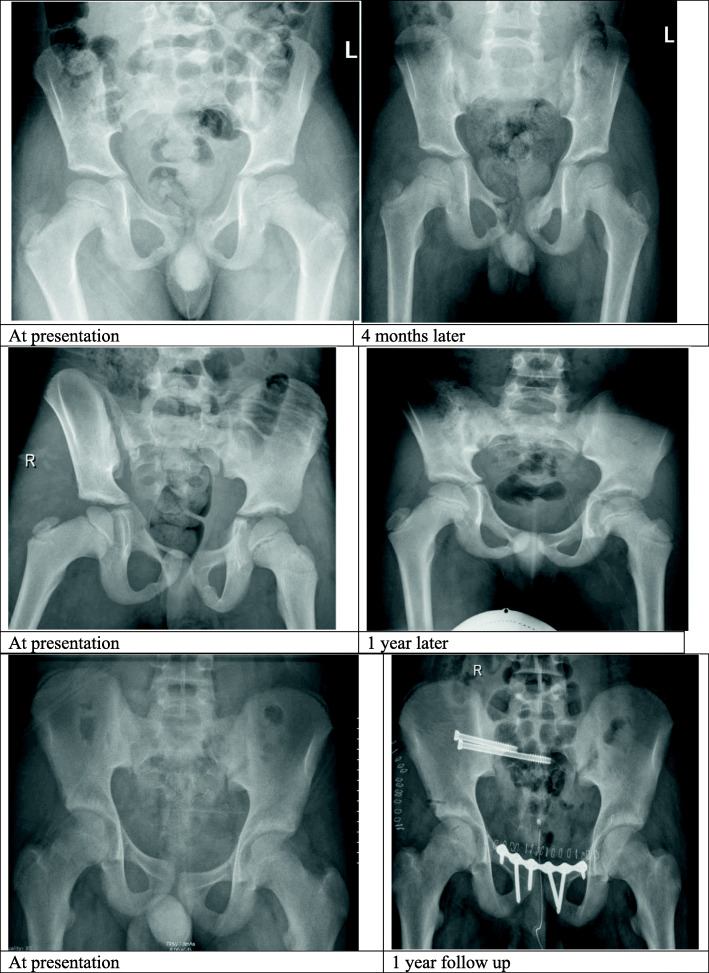

Fig. 2.

Hip X-ray before and after treatment of pediatric pelvic fractures: the upper panel shows Torode type III, treated non-operatively by non-weight bearing for 6 years old patient. The middle panel shows Torode type IV, treated by skeletal traction in 8 years old patient. The lower panel shows Torode type IV, treated by open reduction and internal fixation in 14 years old patient